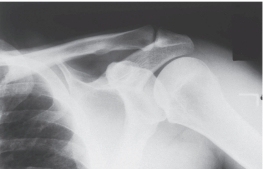

-Refer to the figure. Name the radiographic projection.

A) Anteroposterior external rotation

B) Lateral view of the scapula

C) Anteroposterior internal rotation

D) Axillary view of glenohumeral joint

Anteroposterior internal rotation

3

-Refer to the figure. You have chosen the correct answer because you recognized what region of anatomy seen in profile?

A) Greater tuberosity

B) Acromioclavicular joint

C) Lesser tuberosity

D) Coracoid process

Lesser tuberosity